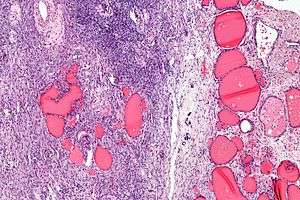

| Micrograph of a struma ovarii. Characteristic thyroid follicles are seen on the right, and ovarian stroma on the left. H&E stain. | |

Low mag.